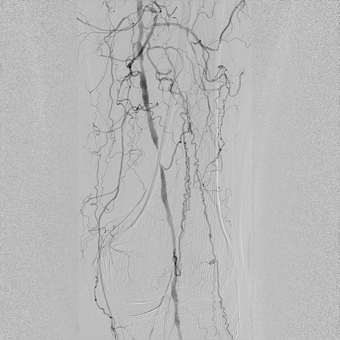

— У пациентов с синдромом диабетической стопы, к сожалению, чаще выполняется ампутация конечности, чем попытка восстановления кровотока в пораженной конечности. Хотя на сегодняшний день возможности сосудистой и эндоваскулярной хирургии позволяют если не сохранить конечность целиком, то хотя бы сберечь ее опорную функцию, тем самым сохранив пациенту мобильность, а значит и высокое качество жизни. Эта пациентка поступила к нам с сухой гангреной без инфицирования 1, 2, 3 пальцев правой стопы 2А степени по классификаци Техасского университета. Была предпринята попытка эндоваскулярной реконструкции пораженных артерий бедра и голени, критическое сужение или окклюзия которых и приводит к синдрому диабетической стопы и необходимости ампутации. Нами была выполнена реканализация подколенной, передней большеберцовой артерии и малоберцовой артерии правой ноги. Полностью пройти подошвенную дугу и заднюю большеберцовую артерию не удалось, но, несмотря на это, полностью был восстановлен кровоток в стопе и пальцах.

![]() Окклюзия артерий голени |

![]() Реканализация передней большеберцовой артерии и малоберцовой артерии; проходимость артерий голени восстановлена |